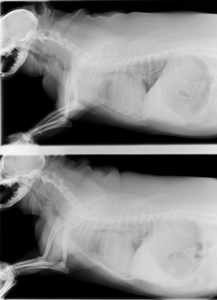

すぐに酸素吸入処置を行い、その後レントゲン検査にて頸部気管が潰れている気管虚脱を起こしていることが分かりました。

吸気、呼気状態の両方とも頸部の気管が潰れています。これでは呼吸もうまくできません。